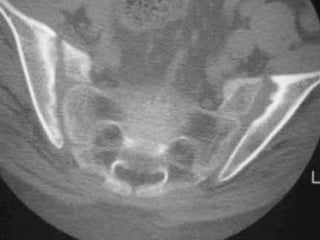

Sacroiliitis

 30 year old man with LBP HLAB27+

Synovitis, subchondral edema, iliac side more common